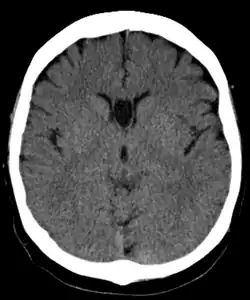

The cave of septum pellucidum (CSP), cavum septi pellucidi, or cavity of septum pellucidum is a slit-like space in the septum pellucidum that is present in fetuses but usually fuses during infancy. The septum pellucidum is a thin, laminated translucent vertical membrane in the midline of the brain separating the anterior horns of the right and left lateral ventricles. It lies posterior to the corpus callosum. Persistence of the cave of septum pellucidum after infancy has been loosely associated with neural maldevelopment and several mental disorders that correlate with decreased brain tissue.[1][2][3][4][5]

The cave of septum pellucidum is bounded anteriorly by the genu of the corpus callosum, superiorly by the body of the corpus callosum, posteriorly by the anterior limb and pillars of the fornix, inferiorly by the anterior commissure and the rostrum of the corpus callosum, and laterally by the leaflets of the septum pellucidum.[6]

There are individual differences in the degree of CSP; whereas some have complete closure of the cavum, others present with a small degree (4–6 mm wide, in the coronal plane) of incomplete closure.[4] The most common type of CSP is noncommunicating; that is, it does not connect to the brain's ventricular system. Because of this lack of communication, the previous use of the term "fifth ventricle" is no longer used, and the fifth ventricle is the name often used for the terminal ventricle.